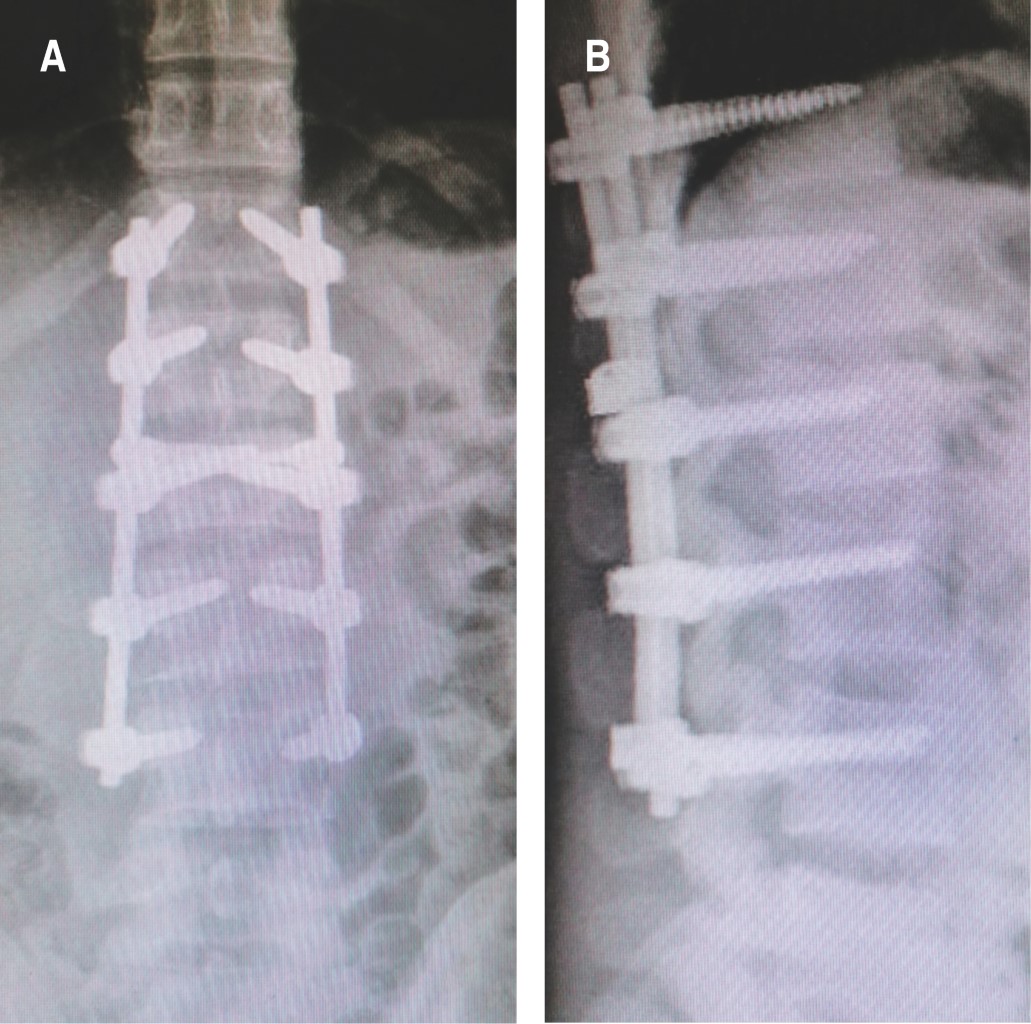

Figure 1